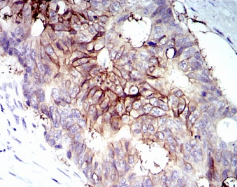

IGF1R-Beta Mouse Monoclonal antibody[3G5C1]

Immunogen :   Purified recombinant fragment of IGF1R-Beta (AA: 1101-1367) expressed in E. Coli.

IHC    1/200 - 1/1000